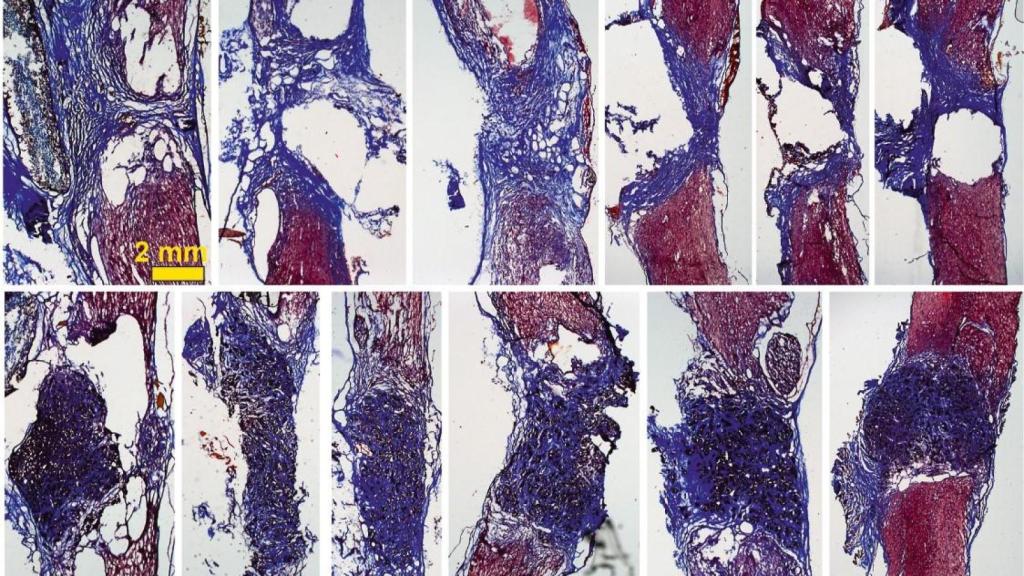

Imagen científica facilitada por el Sescam.

De esta manera, cuando se coloca el scaffold en la médula espinal -en este caso en un modelo de rata con la médula espinal completamente seccionada a nivel torácico-, "vemos que aparecen gran cantidad de vasos sanguíneos, que son fundamentales para nutrir el nuevo tejido, y neuritas (los filamentos que unen unas neuronas con otras)".

La investigadora explica que con esto observan "cómo las neuronas que han sobrevivido en la zona alrededor de la lesión proyectan sus prolongaciones a través del scaffold y lo invaden en toda su extensión 3D". Todo esto, además, mejora con el tiempo: los resultados son incipientes tras 10 días de implante, pero son mucho más evidentes a los 4 meses.

"Nuestros scaffolds de óxido de grafeno reducido favorecen el crecimiento de vasos sanguíneos más abundantes y más grandes, y neuritas más abundantes, más largas y, además, distribuidas de manera más homogénea en el espacio de la lesión", celebra Conchi Serrano.